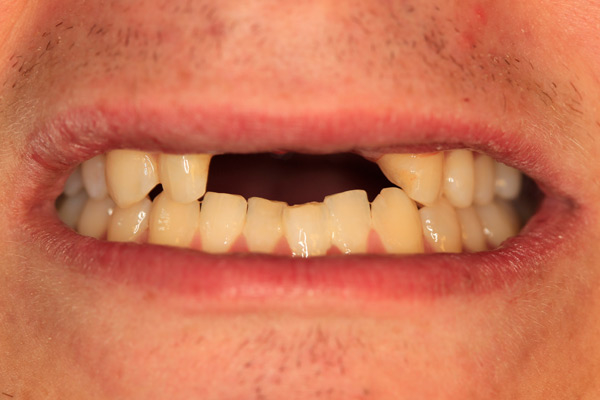

Problem: This young man was hit by a car while riding his bike. He had multiple fractures in his jaw and three front teeth were fractured.

Plan: Our plan… his fractures were fixed. The trauma left a bony defect which was grafted as well as soft tissue VIP grafts. Placed three separate implants with guided surgery. Molded the tissue and placed Zirconium abutments with porcelain crowns.

A great young man with a confident smile.